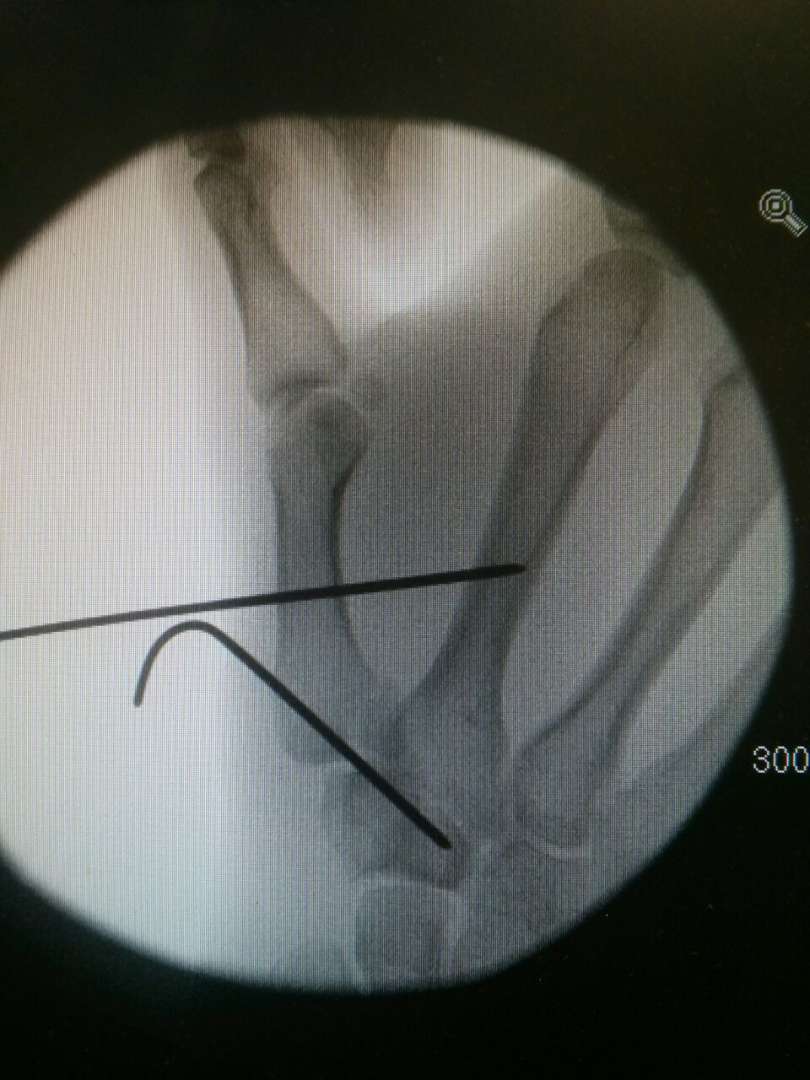

Like you say, treatment usually involves some kind of fixation. Typically a K-wire approach that keeps things in place while healing.

Did mine in mid-September 2014. Bennetts fracture. Broke it on the Saturday*, surgery on the Tuesday. Two pins to keep my thumb in place. Around 6 weeks in plaster. Non-dominant hand so still managed to wipe my own arse. Back at work a couple of days later. Looking back at Strava, my first ride back was commuting after 8 weeks and I remember that being sore, no proper MTB ride until the festive break (approx 12 weeks post injury). Hand remained swollen for ages afterwards and I still have a (very) small bit of restricted movement now - natural resting position for of thumb is it sticks out a bit more than before. Feels tighter even now if I stretch my thumb tip over to touch my pinkie, for example.

Cheers for all the support. Hopefully going in to get it wired together next Friday (I will believe it when I see it). Then 4 weeks till pins come ou t and another 2 weeks in plaster after that. Buggeration